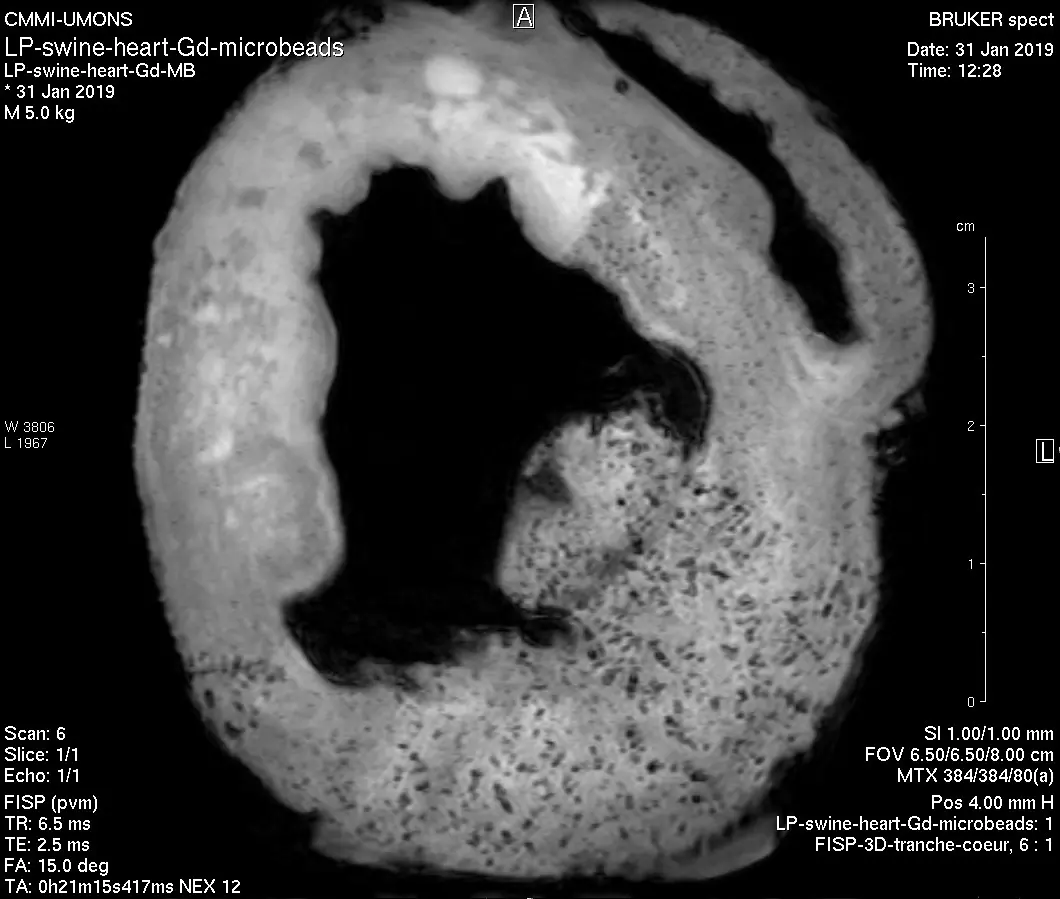

- 9.4T MRI

Bruker, Biospec 94/20, equipped with mouse head & body, rat body & surface 1H coils, 19F/1H mouse body coil, 13C/1H surface coil. - 1T MRI